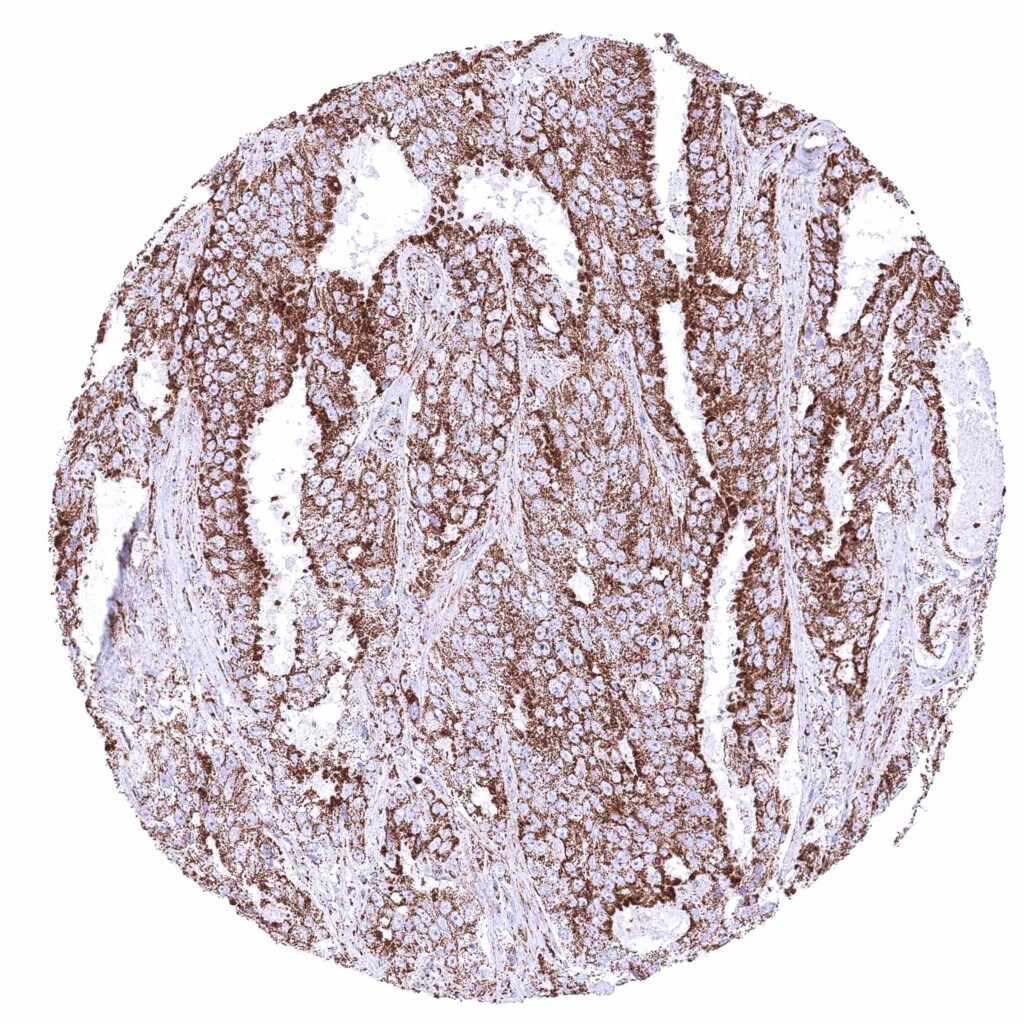

Stomach – Gastric adenocarcinoma (intestinal type) with strong cytoplasmic ATP5J staining of all tumor cells.